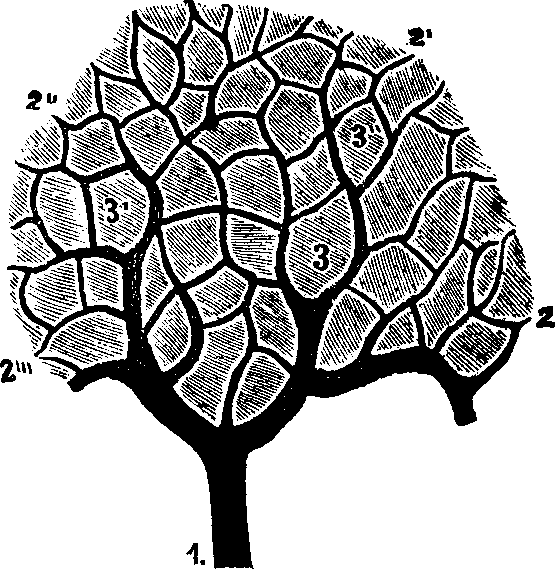

Various opinions have been entertained in regard to the formation, or growth, of bone. Some anatomists have supposed that all bone is formed in cartilage. But this is not true, for there is an intra-membranous, as well as an intra-cartilaginous, formation of bone, as may be seen in the development of the cranial bones, where the gradual calcification takes place upon the inner layers of the fibrous coverings. Intra-cartilaginous deposit is found in the vicinity of the blood-vessels, within the cartilaginous canals; also, there are certain points first observed in the shafts of long bones, called centers of ossification. These points are no sooner formed than the cartilage corpuscles arrange themselves in concentric zones, and, lying in contact with one another, become very compact. As ossification proceeds, the cup-shaped cavities are converted into closed interstices of bone, with extremely thin lamellæ, or layers. These, however, soon increase [pg 21]in density, and no blood-vessels can be observed within them.

Fig. 7. Vertical section of

cartilage near the surface of ossification. 1. Ordinary appearance

of the temporary cartilage. 1'. Portion of the same more highly

magnified. 2. The cells beginning to form into concentric zones.

2'. Portion more magnified. 3. The ossification is extending

in the inter-cellular spaces, and the rows of cells are seen resting in the

cavities so formed, the nuclei being more separated than above. 3'.

Portion of the same more highly magnified.

Fig. 8. Thigh-bone, sawn open lengthwise.

Fig. 9. Lower end of the

thigh-bone sawn across, showing its central cavity.

The bony plates form the boundaries of the Haversian, or nutritive canals of the bones. In the second stage of ossification, the cartilage corpuscles are converted into bone. Becoming flattened against the osseous lamellæ already formed, they crowd upon one another so as to entirely obliterate the lines that distinguish them; and, simultaneously with these changes, a calcareous deposit takes place upon their interior. Bones grow by additions to their ends and surfaces. In the child, their extremities are [pg 22]separated from the body of the bone by layer of cartilage, and the cancellated, or cellular structure, which remains for a time in the interior, represents the early condition of the ossifying substances.

We are not less interested in tracing the formation of bone through its several stages, than in considering other parts of the human system. The formation of the Haversian canals for the passage of blood-vessels to nourish the bones, the earlier construction of bony tissue by a metamorphosis of cartilaginous substance, and also the commencement of ossification at distinct points, called centers of ossification, are all important subjects, requiring the student's careful attention. The bones are protected by an external membranous envelope, which, from its situation is called the periosteum. The bones are divided into four classes, long, short, flat and irregular, being thus adapted to subserve a variety of purposes.